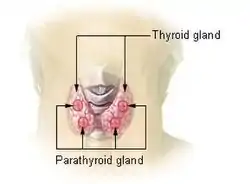

| Thyroid and parathyroid | |

The parathyroid is composed of 4 glands with 2 located superiorly and 2 located inferiorly.[27] The parathyroid glands are located on the posterior thyroid and are derived from the endoderm of the 3rd and 4th pharyngeal pouches.[27] Specifically, the inferior parathyroid glands are derived from the 3rd pharyngeal pouch and the superior parathyroid glands are derived from the 4th pharyngeal pouch dorsal wing.[28] The ultimopharyngeal body is derived from the 4th pharyngeal pouch ventral wing and the parafollicular cells ( C-cells) are derived when the ultimopharyngeal bodies fuse with the posterolateral thyroid.[28] The parathyroid glands separates from the pharyngeal wall and attaches to the posterior thyroid during the 7th week of human embryonic development.[27]